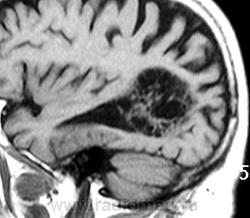

ГМ. Субэпендимома 2. +

Субэпендимома